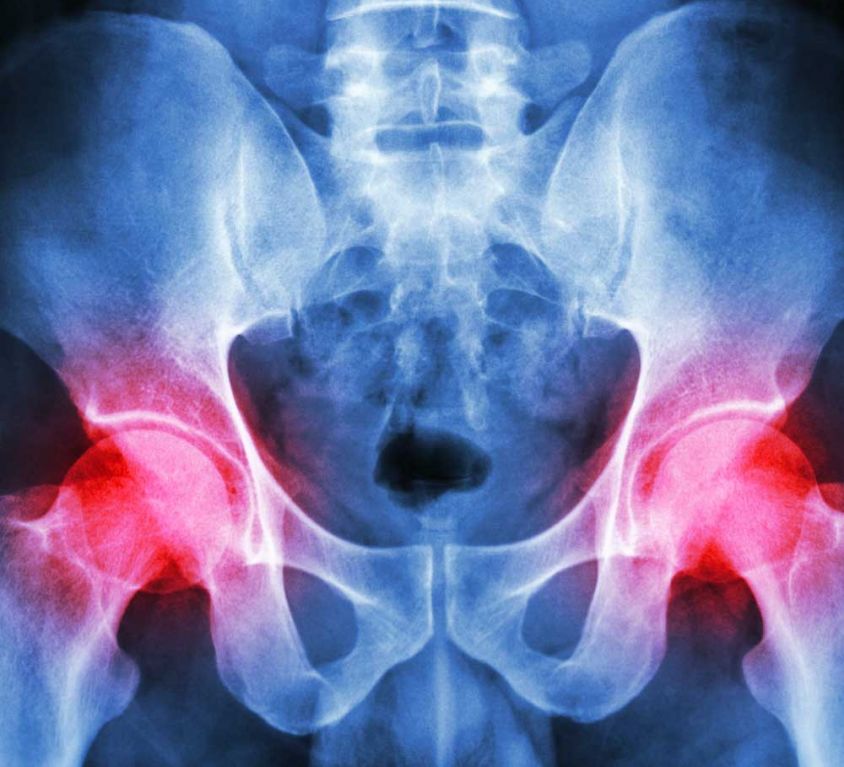

Hip injury and disease, although typically associated with the elderly, can affect anyone. Painful hip conditions can have an impact on the thigh bone (femur), pelvic bone, nerves, muscles, joints, ligaments, blood vessels, and internal organs.

The hip is a complicated joint made up of bone, cartilage, ligaments, muscle, and a lubricating fluid. The symptoms of a hip disorder will differ depending on the cause of the disorder and the part of the hip joint that’s causing problems. Common symptoms of a hip disorder include: